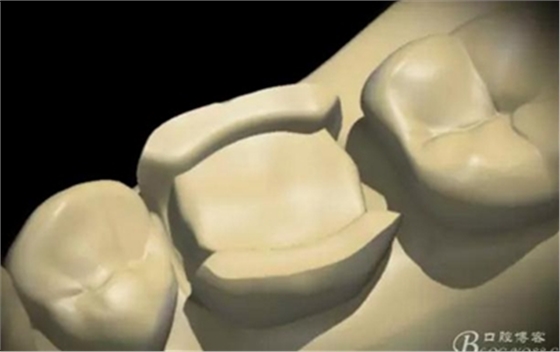

制作完成

高嵌體